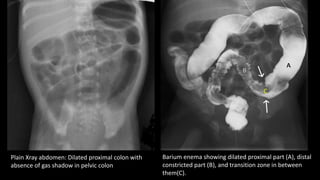

Plain X-ray of abdomen

• Dilated proximal colon with absence of gas shadow in pelvic colon.

Barium enema

• Shows a transition zone in between dilated proximal

colon and small caliber distal colon.

• Rectal diameter is the same as or smaller than the sigmoid

Plain Xray abdomen: Dilated proximal colon with

absence of gas shadow in pelvic colon

Barium enema showing dilated proximal part (A), distal

constricted part (B), and transition zone in between

them(C).